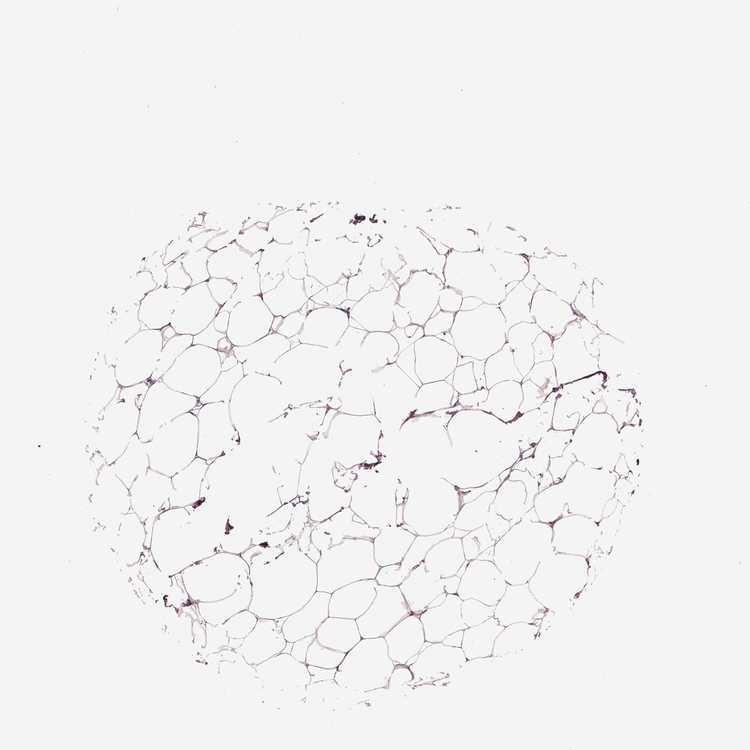

BREAST - Antibody stainingi

Antibody staining in the annotated cell types in the current human tissue is reported as not detected, low, medium, or high, based on conventional immunohistochemistry profiling in selected tissues. This score is based on the combination of the staining intensity and fraction of stained cells.

Each image is clickable and will lead to virtual microscopy that enables deeper exploration of all samples and also displays staining intensity scores, fraction scores and subcellular localization as well as patient and tissue information for each sample.

Antibody HPA073619

Adipocytes Not detected

Glandular cells Not detected

Myoepithelial cells Not detected